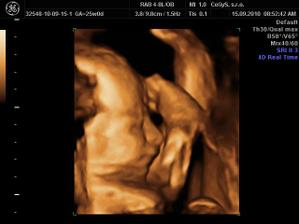

Náš anjelik🙂